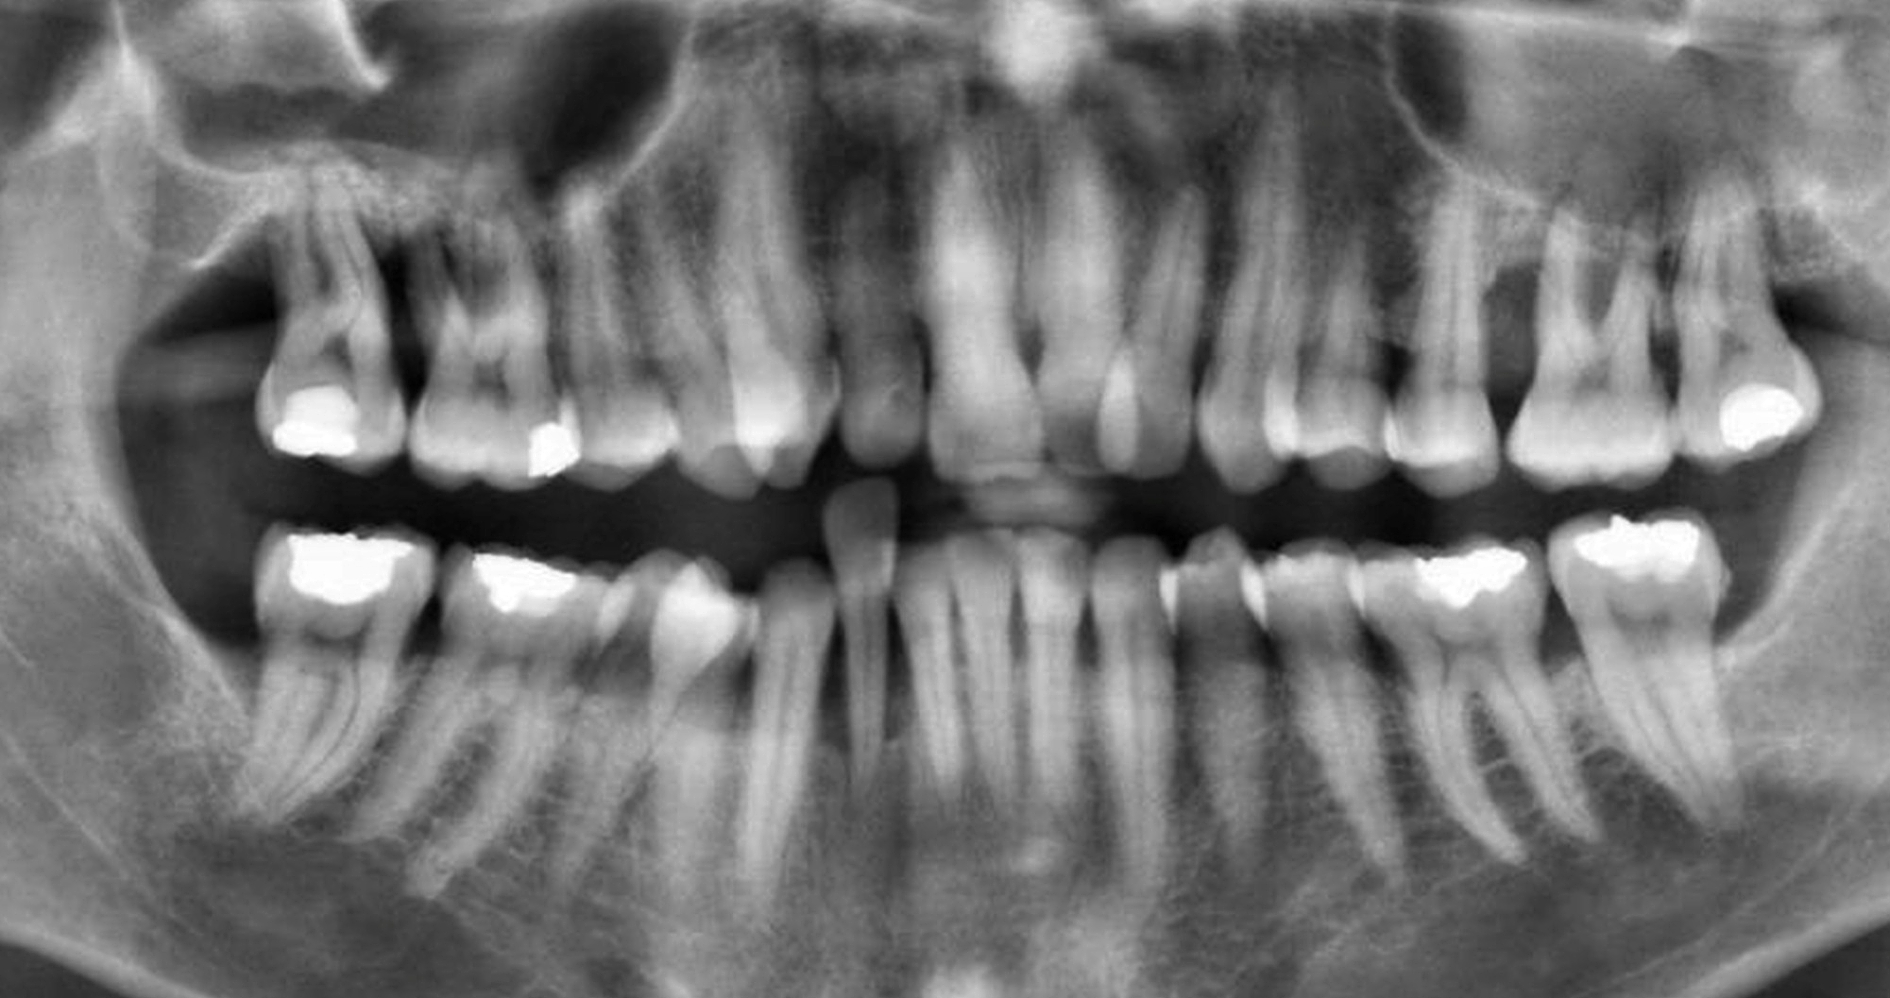

Fallstricke in der Endodontologie

Die endodontische Therapie stellt hohe Anforderungen an Diagnostik, Planung und technische Umsetzung, bietet jedoch bei leitliniengerechtem Vorgehen eine prognostisch günstige und substanzschonende Möglichkeit zum Zahnerhalt.…